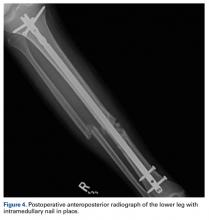

Closed reduction and removal of the fibula fragment were attempted multiple times, to no avail. A limited open approach was deemed necessary, and an incision was made anterior to the fracture site. The soft tissue over the fracture segment was bluntly dissected until the point of intussusception was palpated and visualized. A bone hook was used to dislodge the fibula from the tibial diaphysis (Figure 3).After the fibula was liberated, additional closed manipulative reduction techniques were used on the tibia to restore length, alignment, and rotation, and an appropriately sized nail was advanced distally past the fracture segment and fixed with interlocking screws proximally and distally (Figure 4).